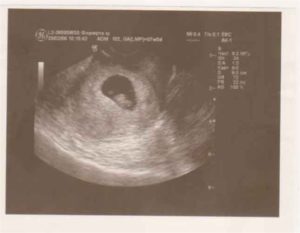

УЗИ на 7 неделе беременности.

На седьмой неделе беременности УЗИ показывает не только рост эмбриона, но и все изменения, которые произошли с ним за эти недели. К УЗИ на данном сроке прибегают при наличии показаний — угроза прерывания, уточнение срока беременности при несоответствии размеров матки предполагаемому сроку. Оценивается сердцебиение, размеры эмбриона.

Фото УЗИ на 7 неделеЧетко просматривается желточный мешок, он имеет светлый контур, его содержимое визуализируется в виде темного пятна. Благодаря желточному мешку ваш малыш получает необходимые питательные вещества, аминокислоты, белки и микроэлементы. Учащается сердцебиение до 110 – 130 ударов в минуту.

Объясняется это развитием сердца малыша. В большинстве случаев УЗИ проводится трансвагинально, так как оно дает более информативные данные о развитии беременности, состоянии желтого тела, сердцебиении малыша.